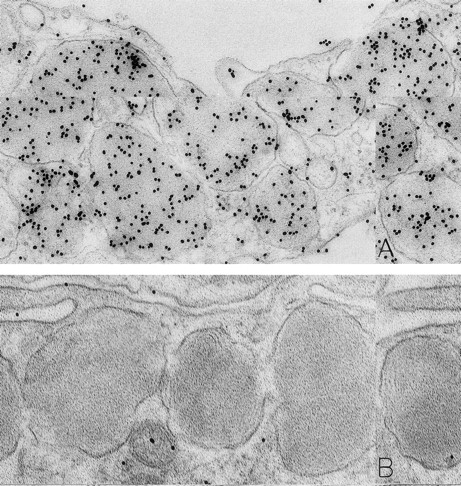

Mast cells in skin biopsies obtained 1 hour 40 minutes (A) or 2 hours (B) after the SC injection of 25 or 5 μg/kg rhSCF, respectively, in patients no. 3 (A) and no. 1 (B), who had received daily SC injections of rhSCF for 13 days. Reactivity for histamine is indicated by DAO-gold labeling in the cytoplasmic granules of a mast cell that exhibits no morphologic evidence of secretory activity (A); DAO-gold label is absent when the grid containing a section of the specimen was digested with DAO before staining with DAO-gold (B). Original magnifications: (A) ×67,500; and (B) ×75,000.

As noted in our previous reports,6 14 ultrastructural evidence of anaphylactic-type degranulation, including the extracellular extrusion of membrane-free cytoplasmic granules, was observed only in biopsies from sites that had been directly injected with rhSCF. Using the DAO-gold enzyme-affinity method, reactivity (gold label) was very strong in the granules of nonsecretory mast cells (in biopsies of either control or rhSCF-injected sites) as well as in any electron-dense cytoplasmic granules remaining in the cytoplasm of skin mast cells that were undergoing secretion (Figs 1, 2, and 3). Moreover, retention of DAO-gold labeling (indicating the presence of histamine) was evident in cytoplasmic granules that exhibited all of the substructural patterns that can be observed in human skin mast cells (Fig 3). Such patterns include granules with crystal (Fig 3A), scroll (Fig 3B), or mixed patterns.

Specificity controls for the histaminase-gold-based affinity technique, including absorption of the DAO-gold reagent by solid-phase histamine before sample staining (Figs 2C and 3C) and digestion of the section with histaminase before DAO-gold staining (Figs 1B and 3D), showed a marked reduction of label or a complete absence of reactivity. In every case tested, there was no staining of sections with colloidal gold alone (data not shown).